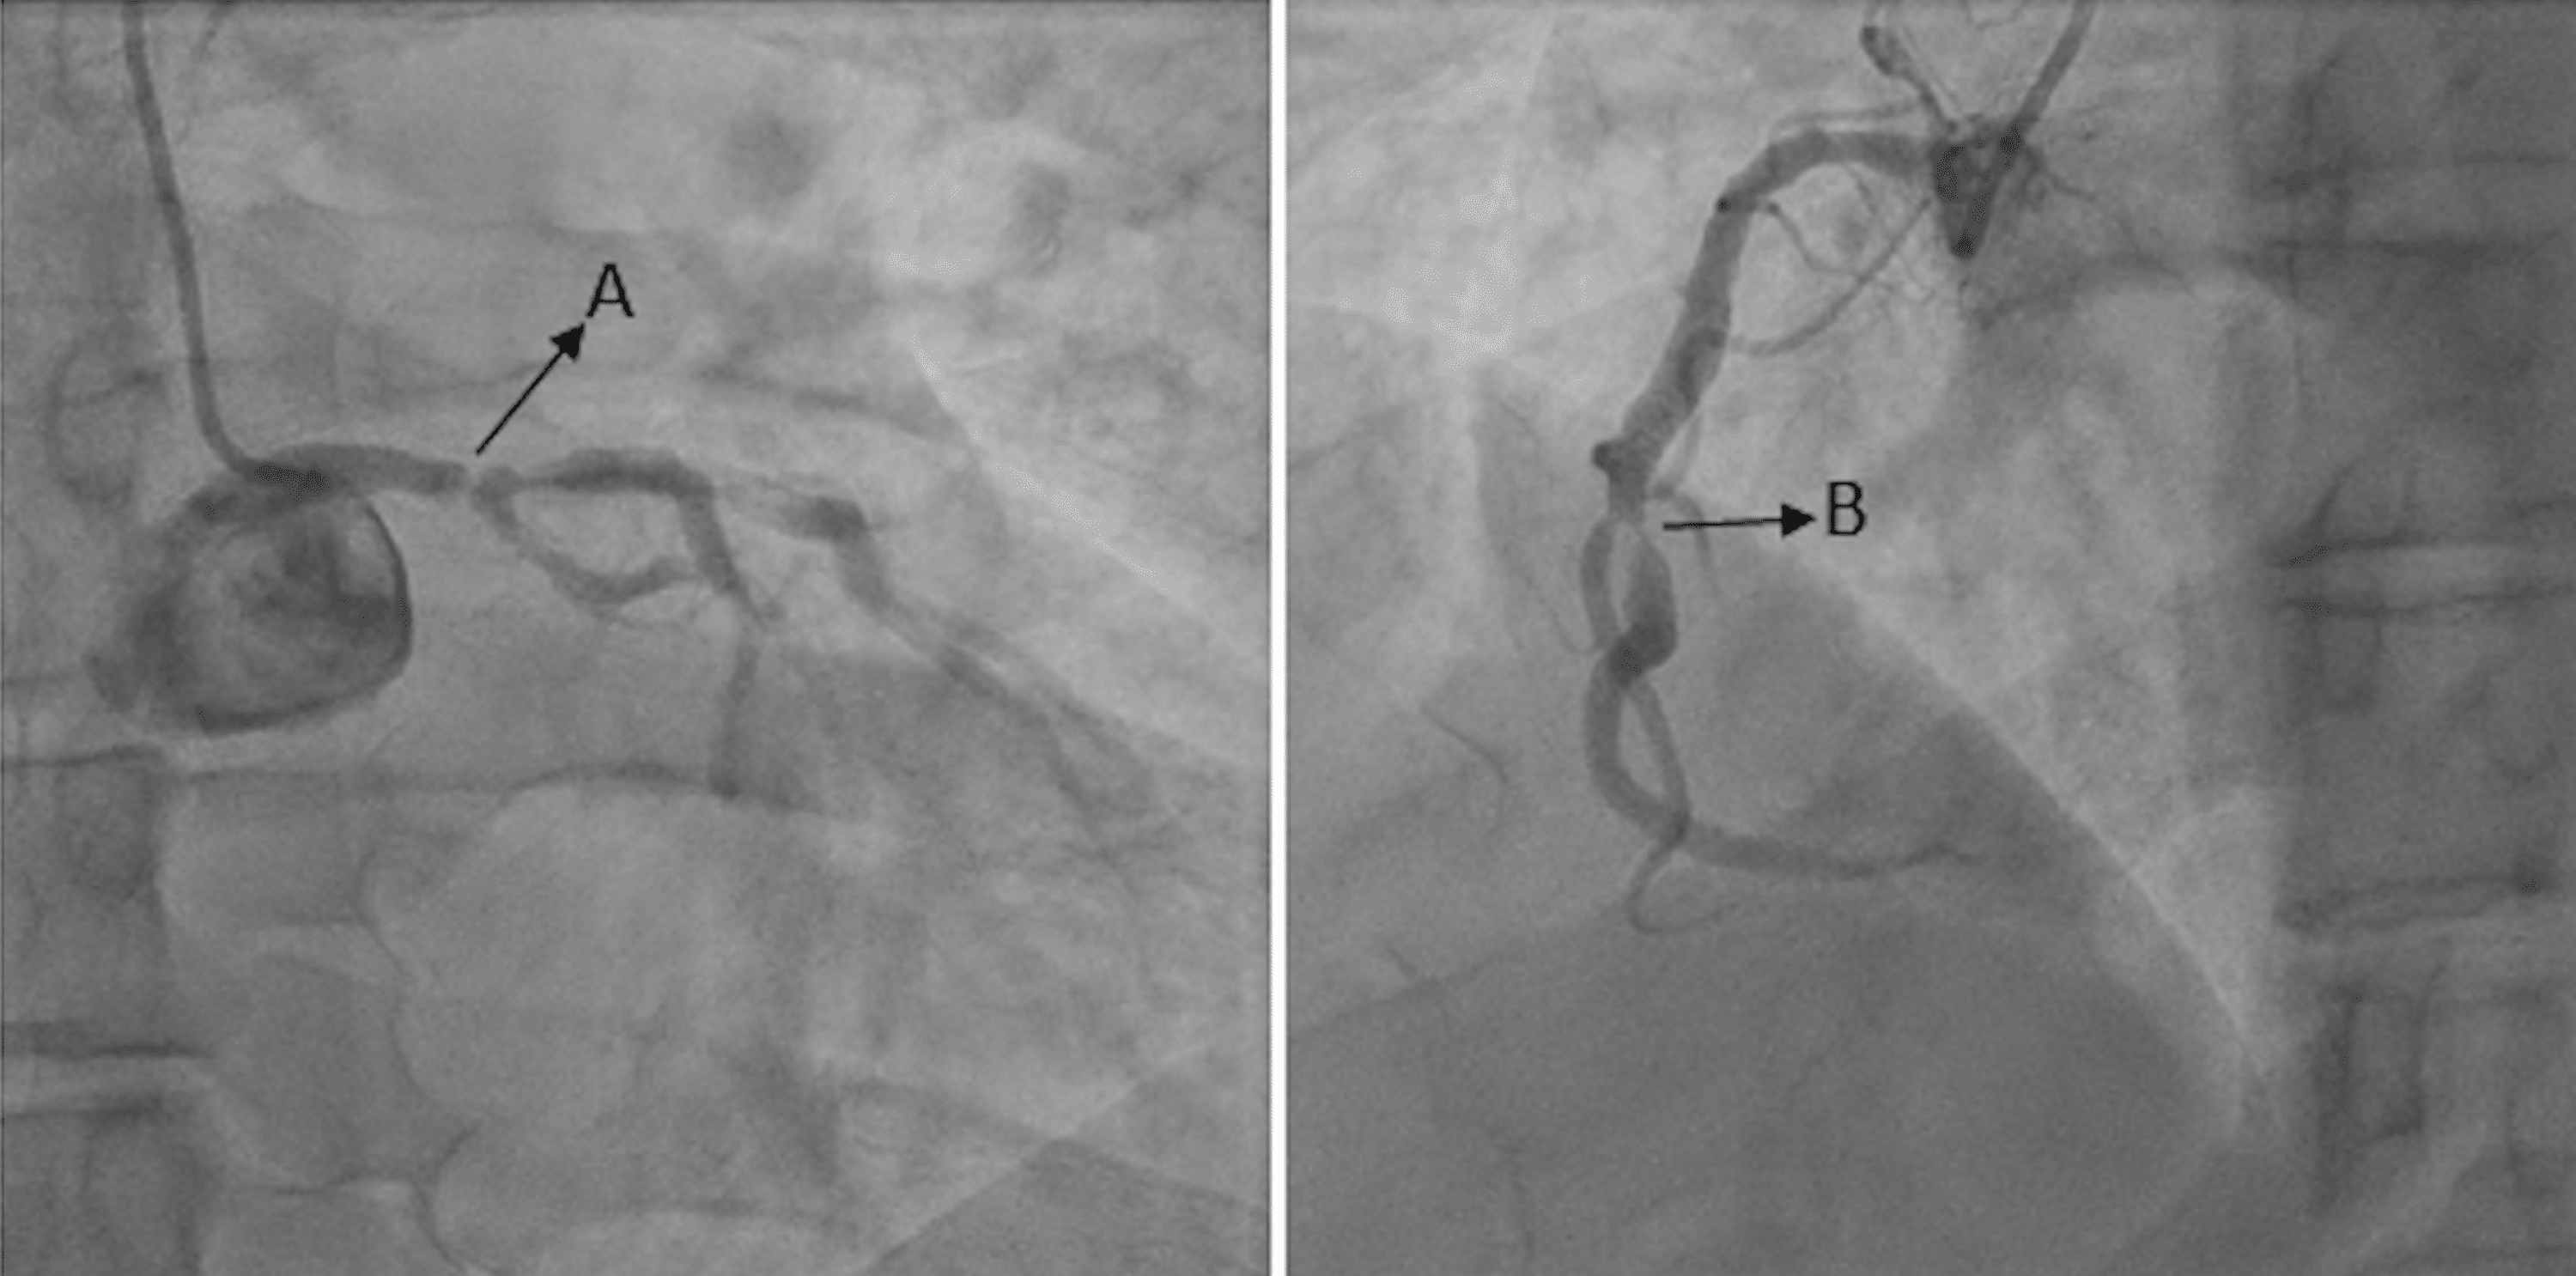

From www.cureus.com

Cureus Positive Regadenoson Stress Test in a Patient on Phentermine With Normal Coronaries Heart Catheterization Stress Test Take a tiny bit of muscle from your. A main objective of stress testing is to assess the functional or physiological consequences of anatomic coronary artery. Current us stable ischemic heart disease guidelines favor noninvasive functional testing for myocardial ischemia in most. Cardiac catheterization is used to: Cardiac catheterization (cardiac cath or heart cath) is a procedure to examine how. Heart Catheterization Stress Test.

Cureus Negative Stress Test Is Not Always Negative Revisiting the Clinical Implications of Heart Catheterization Stress Test If a screening exam, such as an electrocardiogram (ecg) or stress test, suggests there may be a heart condition that needs to be explored further, your healthcare provider may order a cardiac. Current us stable ischemic heart disease guidelines favor noninvasive functional testing for myocardial ischemia in most. Cardiac catheterization is most often performed after completion of a history and. Heart Catheterization Stress Test.